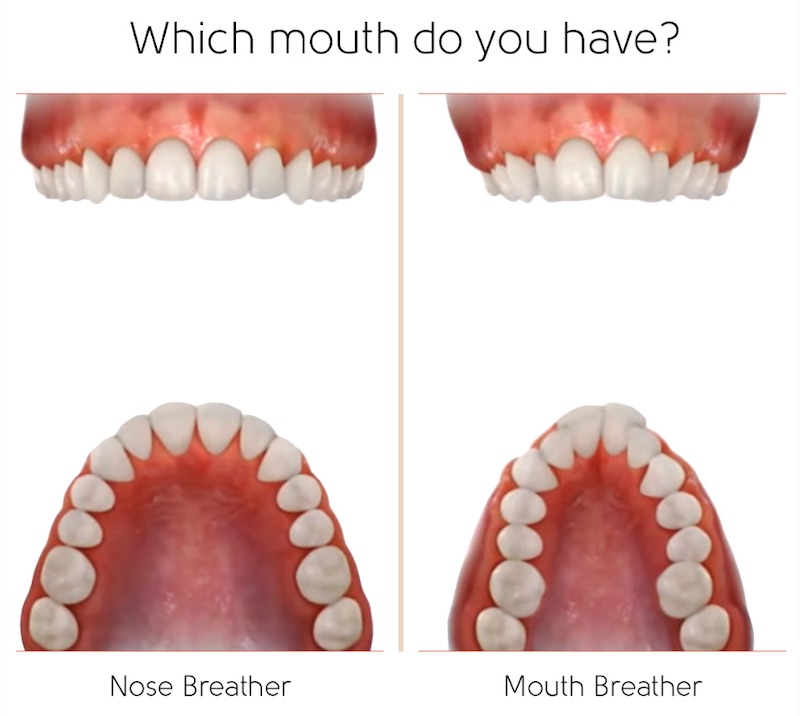

首先,牙齒的外側是我們的臉頰,內側是舌頭肌肉,這兩者之間會形成力的平衡,正常情況下力的平衡會讓牙齒牙弓生長成一個碗公或U的形狀,一個弧形的形狀是力平衡的結果。

左圖是舌頭正常休息位置,輕輕頂在上顎,牙齒內側舌頭和外側臉頰肌肉形成平衡;右圖是舌頭位置太低,導致上牙弓容易坍縮,變成較狹窄的形狀。

左圖為標準的力平衡,牙弓及齒列也會順著力量自然形成U字型。中間圖表示通常若舌頭位置不恰當,或力量較低、外側力較大時,就容易形成如右圖的狹窄型牙弓,而門牙則容易被推擠往前飛去而形成暴牙。

由此可知,力的平衡一旦少了外側力,牙齒就會往外;反之少了內側力則會往內推擠,造成牙弓狹窄,而當牙弓變成V字型時,門牙就容易外飛。